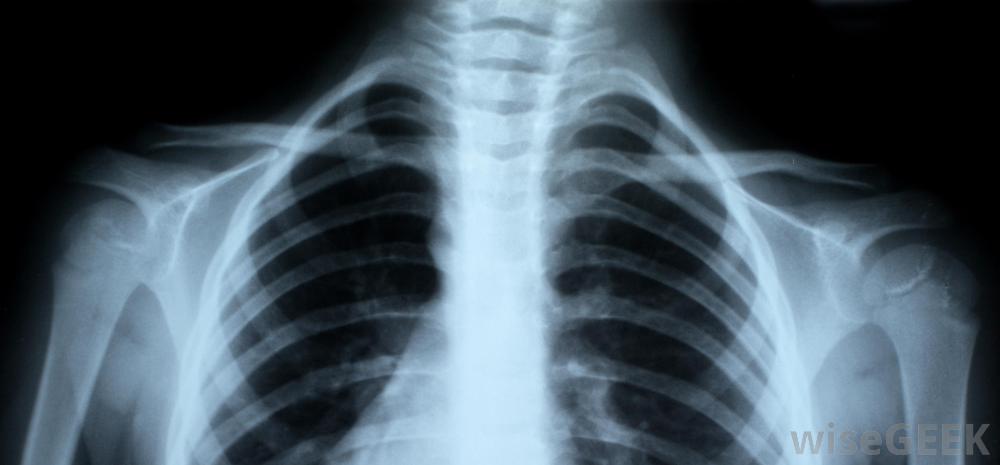

锁骨,也称锁骨,是人体最常见的骨折之一。运动员,儿童,甚至婴儿从产道出来都会经历骨折。治疗骨折的锁骨通常不需要手术,但患者可以采取一些措施来妥善治疗。为了治疗骨折的锁骨,患者应该去看医生以确定是否有骨折。固定手臂、使用冷敷和服用止痛药是治疗的常见部分,一旦疼痛消退,进行一系列的运动训练也可能是必要的人的骨架,包括红色的锁骨。如果一个人觉得自己的锁骨断了,在去看医生之前,他应该尽量保持手臂不动。有时,骨折会导致开放性骨折,也就是说,当骨头穿过皮肤时。如果骨折处有伤口,可能意味着骨头打破了皮肤,但在患者移动时又重新进入。在这种情况下,患者应就医,因为手术可能是清理伤口和防止感染的必要手段。射线照片可以向医生显示锁骨是否断裂锁骨骨折愈合的时间长短取决于患者的年龄儿童通常在三到四周后痊愈。青少年可能在六到八周后痊愈,但是一个成年人可能要等四个月。一条吊带或八字形绷带可能要一直戴着。许多医生更喜欢吊带而不是绷带,因为一个人戴着八字形绷带时不可能正确地清洗,而且绷带会比绷带更不舒服,会引起更多的皮肤刺激。对于锁骨骨折的病人,可能会开出或推荐不同形式的止痛药,冷敷20分钟左右建议每两小时进行一次,以帮助减轻疼痛和减轻肿胀。疼痛消退后,最好开始移动手臂、手腕和肩膀,以防止其僵硬。医生或理疗师可以教患者进行可以保持手臂的锻炼活动。在断开的锁骨完全愈合之前,不应尝试运动和其他力量锻炼。有时手术是治疗锁骨骨折的最佳选择。这通常发生在开放性骨折或者如果骨头没有愈合。在手术过程中,医生可能需要植入钢板或螺丝钉。手术也可能是清理伤口和防止感染的必要手段。然而,锁骨骨折的手术并不常见,而且骨头通常在没有任何干预的情况下愈合使用冷敷和止痛药可以缓解锁骨骨折带来的不适。